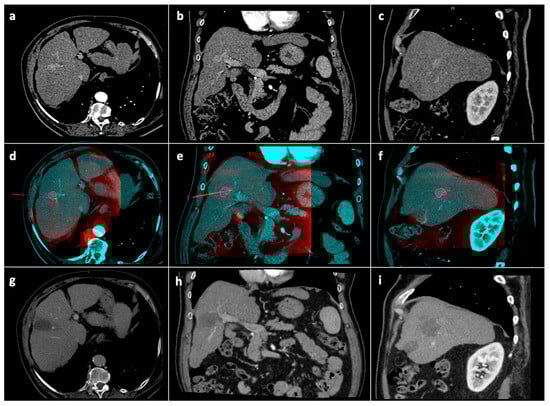

2.1. Procedure